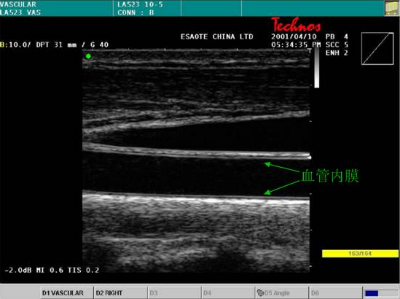

颈动脉超声。通过检查颈动脉内膜中层厚度可预测心脏病。研究提示,颈动脉内膜厚度与冠心病有关,超声检查在血流受阻前就可以早期非常敏感地检测血管病变,因为没有射线,怀孕妇女也可行此检查;如果动脉内膜厚度异常,说明心脏病风险也较高,需要调整饮食、多运动或服降脂药、降压药。